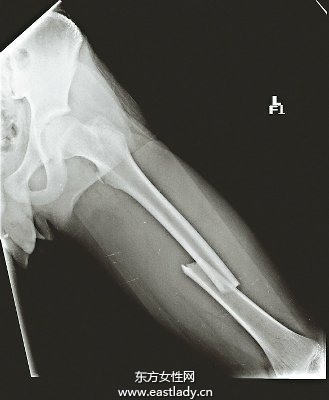

該少年最近兩次搭乘機車發(fā)生小車禍,載他的騎士都無大礙,他被載反而大腿骨發(fā)生骨折。專家研判骨質(zhì)疏松是關(guān)鍵,大腿骨缺乏膠質(zhì)呈現(xiàn)空洞,猶如曬干的絲瓜、匏瓜,醫(yī)護人員都相當吃驚。